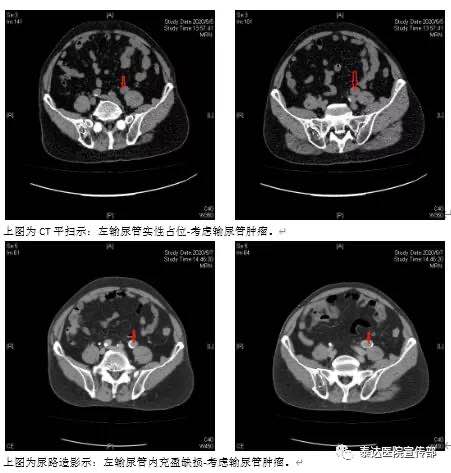

崔大娘,69岁,左腰部不适伴间断血尿,彩超检查发现左肾积水,左输尿管占位入院,入院检查CT示:发现左肾积水,左输尿管下端肿瘤。收入院后给予行常规检查及输尿管镜检查并取活组织做病理检查。

CT扫描具有高分辨力,在平扫及增强扫描后,能清楚地显示病变部位、大小、密度浸润范围及周围器官的关系,对肾盂肿瘤的诊断正确率可达90%以上。肾盂癌和输尿管癌典型CT表现为①肾盂或输尿管内发现软组织肿瘤,可伴有肾盂或输尿管积水,还能发现肾或输尿管周围浸润和区域淋巴结转移;②增强后肿瘤强化不明显。